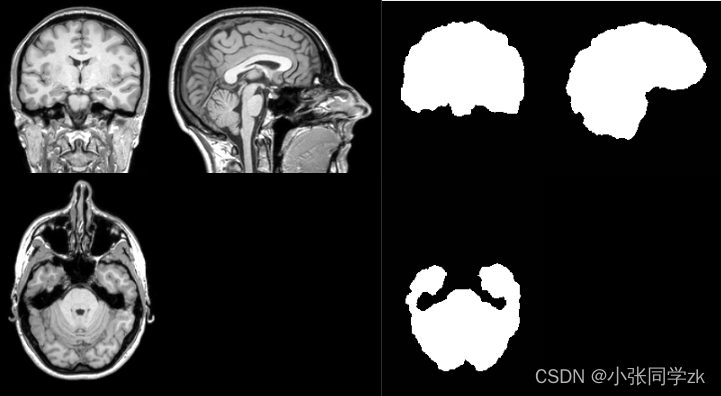

对ICBM152(脑成像国际联盟(International Consortium for Brain Mapping)所提供的标准空间模板)进行颅骨剥离的结果如图2.8.28所示:

图2.8.28 颅骨剥离